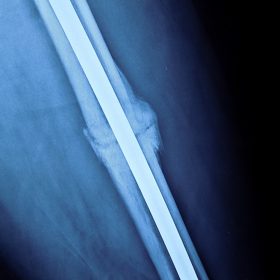

Τα κατάγματα της Διάφυσης των οστών της κνήμης και του Μηριαίου οστού στη σύγχρονη ΟΡΘΡΟΠΑΙΔΙΚΗ αντιμετωπίζονται με ΕΝΔΟΜΥΕΛΙΚΗ ΗΛΩΣΗ.

Δύο τομές 3 εκατοστών και 1 εκατοστού αντιστοίχως για την εισαγωγή και το κλείδωμα του ήλου μέσα στο οστό. Η μέθοδος είναι κλειστή,σχεδόν αναίμακτη,διάρκειας 60 λεπτών,με τη βοήθεια C-ARM (τηλεόρασης).